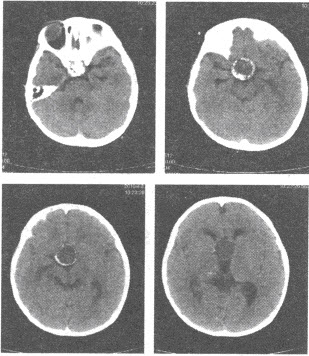

患儿,男,5岁,CT平扫图像如下,最可能的诊断是()

A:垂体瘤

B:透明隔囊肿

C:颅咽管瘤

D:蛛网膜囊肿

E:Rathke裂囊肿